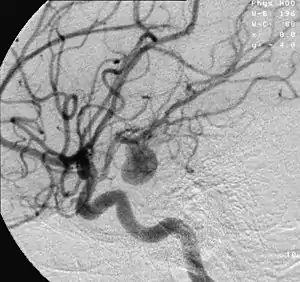

| Angiography of an aneurysm in a brain artery. The aneurysm is the large bulge in the center of the image. | |